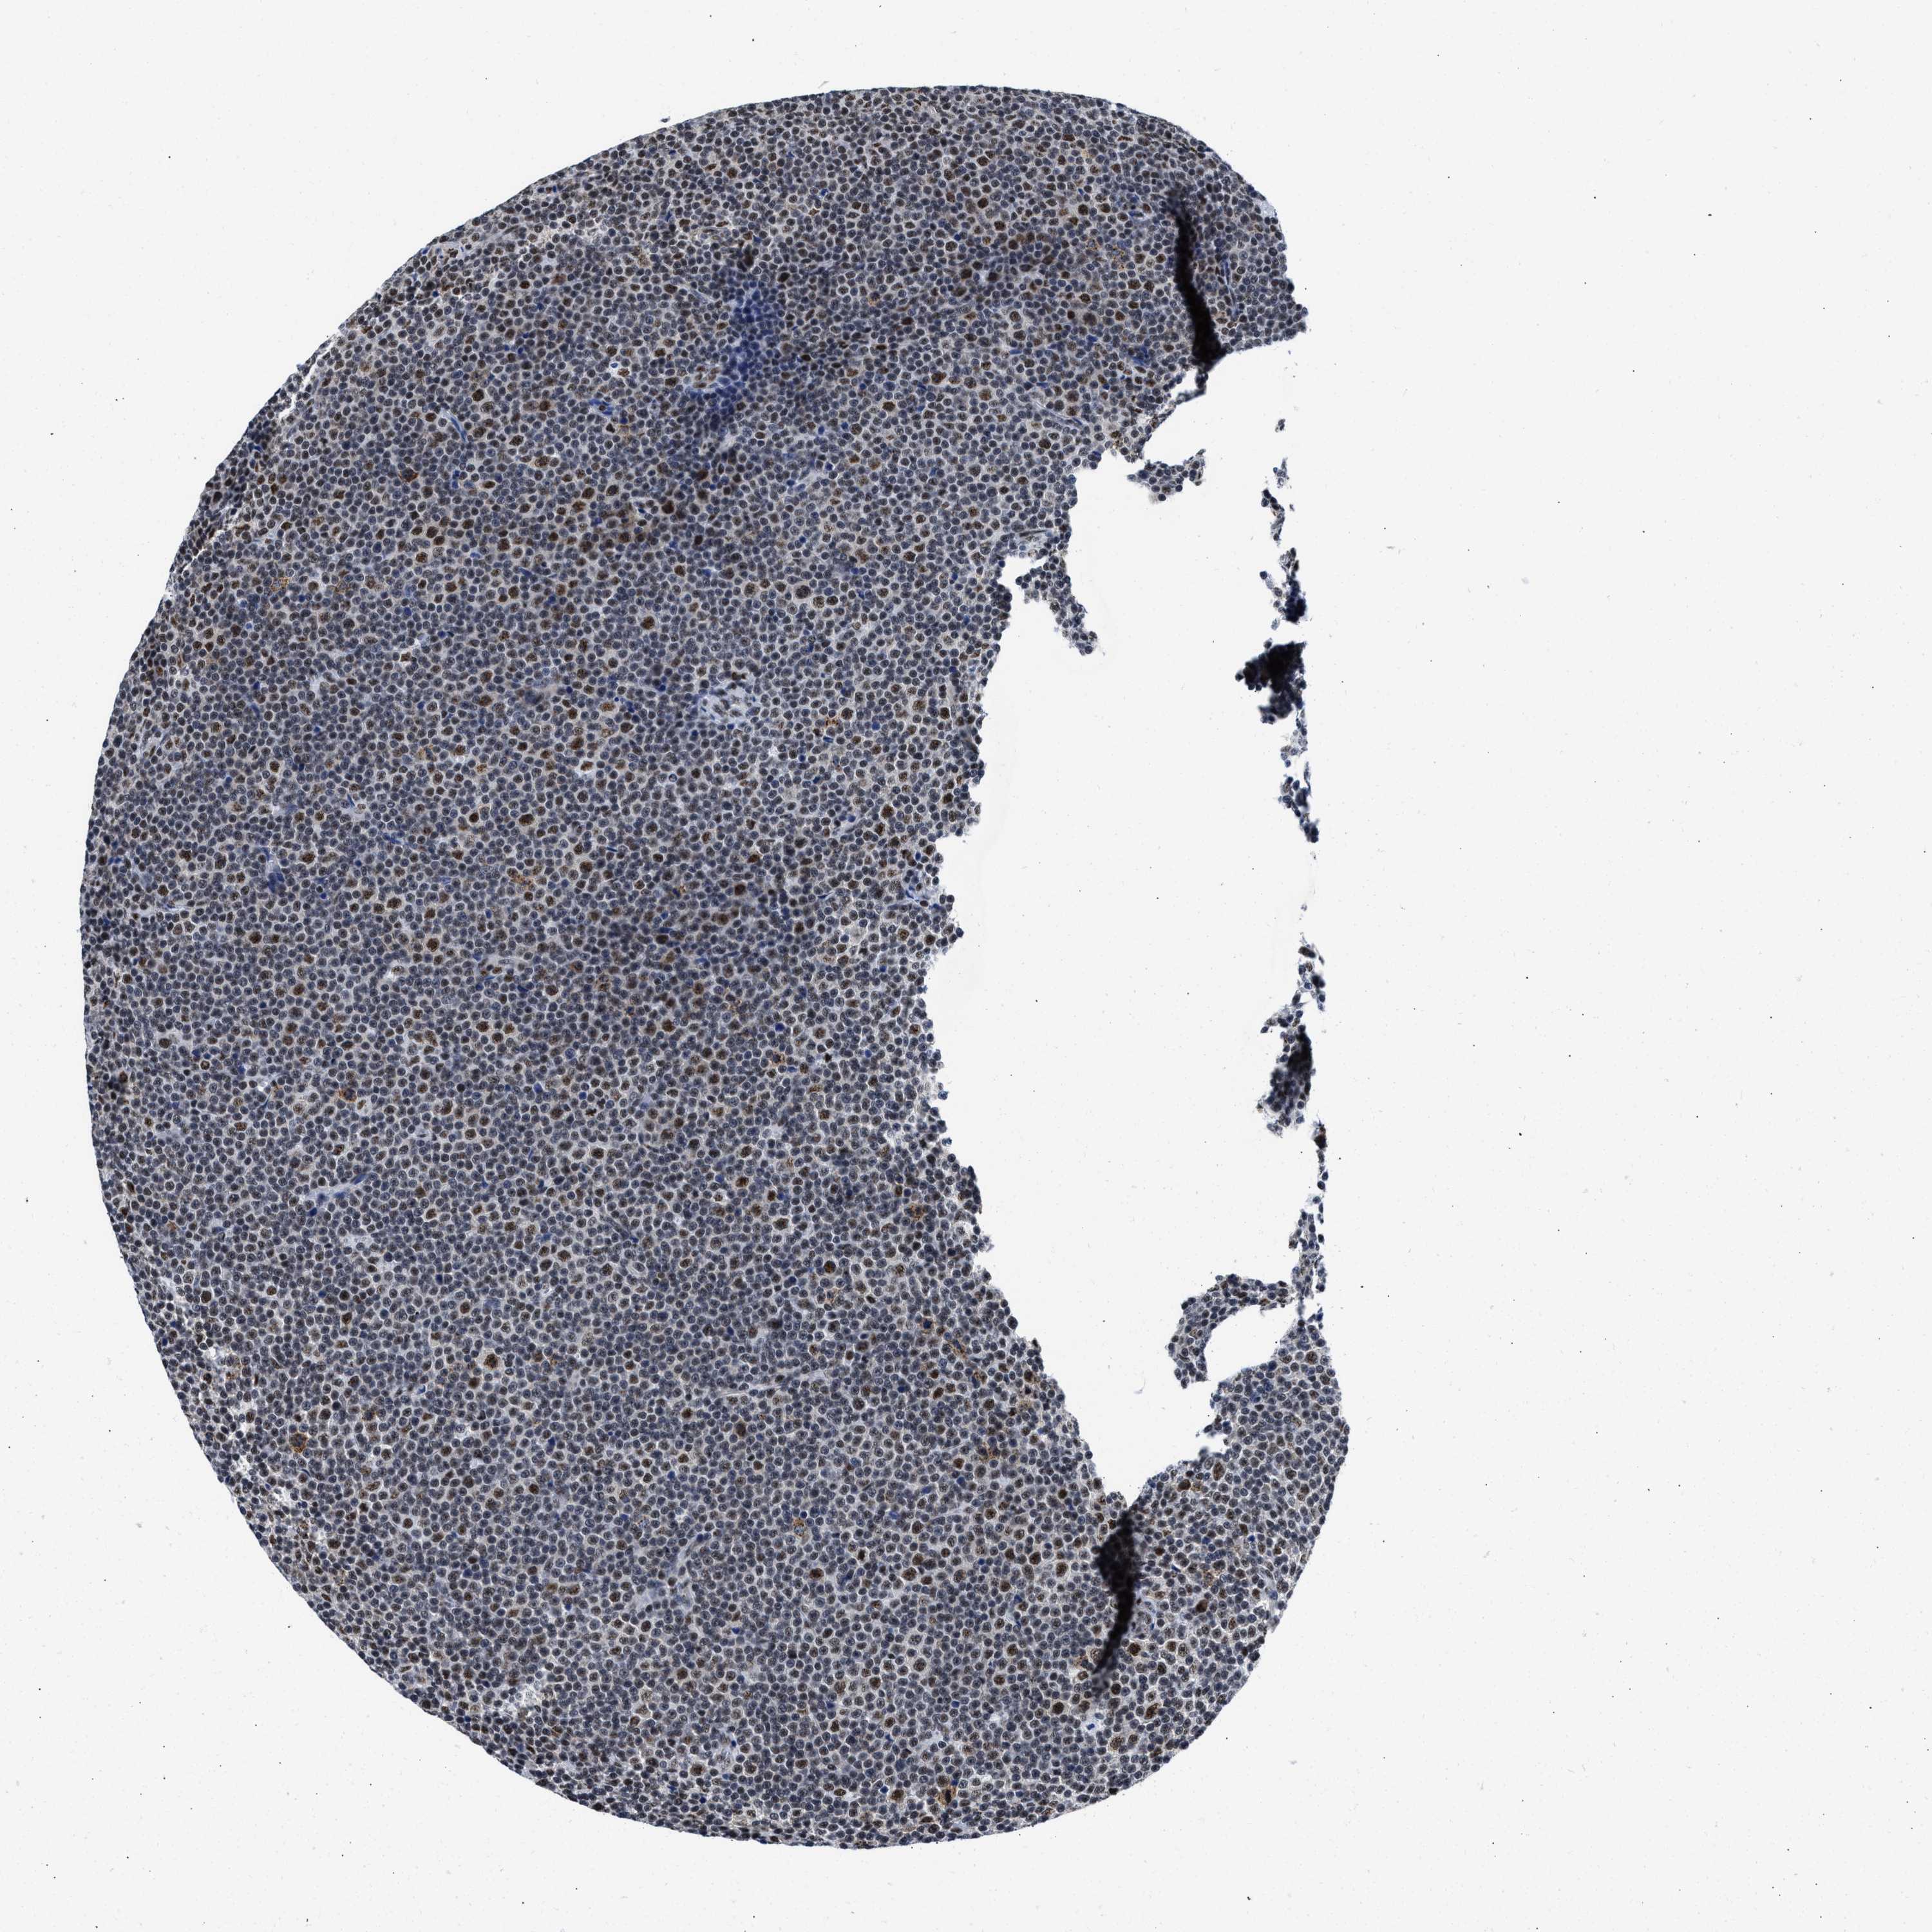

LYMPHOMA - Protein expressioni

A mouse-over function shows sample information and annotation data. Click on an image to view it in a full screen mode. Samples can be filtered based on level of antibody staining by selecting one or several of the following categories: high, medium, low and not detected. The assay and annotation is described here.

Each image is clickable and will lead to virtual microscopy that enables deeper exploration of all samples and also displays staining intensity scores, fraction scores and subcellular localization as well as patient and tissue information for each sample.

Antibody HPA018403

Staining

High

Intensity

Strong

Quantity

>75%

Location

Nuclear

Hodgkin's disease, NOS

Malignant lymphoma, non-Hodgkin's type, High grade

Malignant lymphoma, non-Hodgkin's type, Low grade